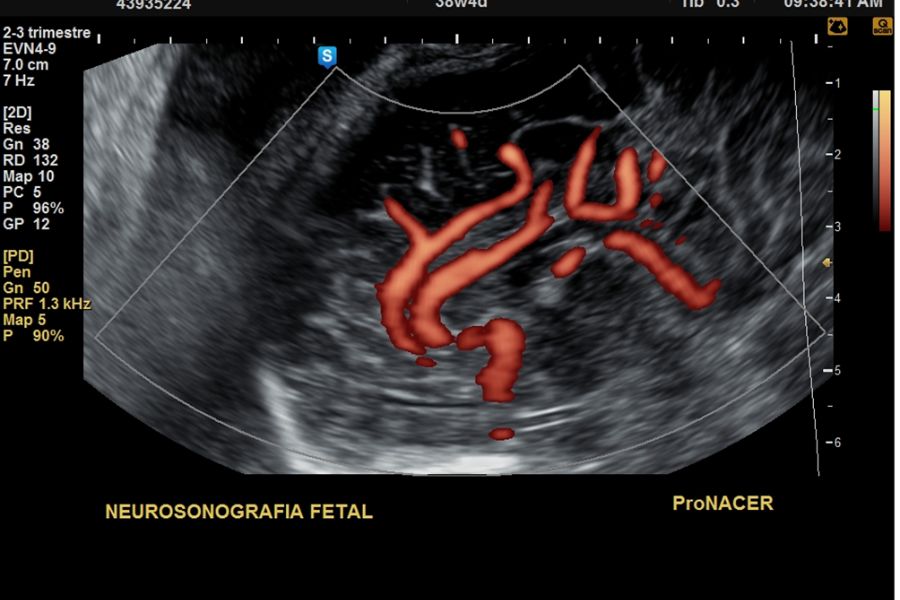

Neurosonografía fetal : Desde las 20 a 41 semanas

Neurosonografía fetal: Desde las 20 a 41 semanas